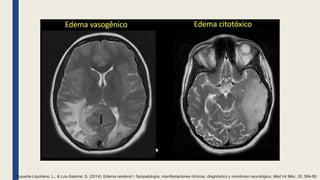

Esqueda-Liquidano, L., & Loo-Salomé, S. (2014). Edema cerebral I: fisiopatología, manifestaciones clínicas, diagnóstico y monitoreo neurológico. Med Int Méx, 30, 584-90.